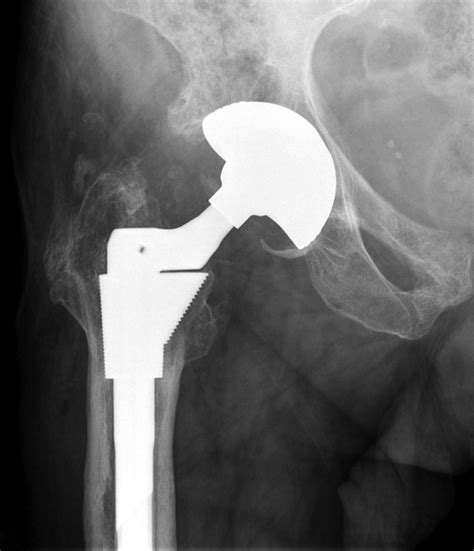

• Implant Placement: The artificial hip components are placed and secured in position. The femoral component is inserted into the thighbone, and the acetabular component is placed in the hip socket.